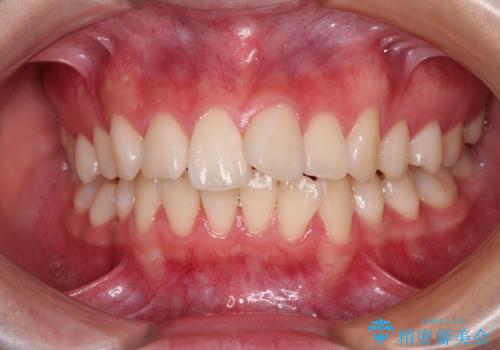

- 急速拡大装置 狭い骨幅を拡大した上で、口元の突出感を改善する抜歯矯正治療

- 【モニター】とがった口元を抜歯して改善 ワイヤー装置の矯正治療- 担当医 藤巻太一朗

- 出っ歯を治したい ワイヤー装置での抜歯矯正- 担当医 藤巻太一朗